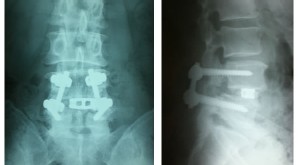

私は十数年前に分離症と側面ヘルニアで手術を受け上の写真のように

第4腰椎をチタンのボルトで固定しています。

固定されてる部分は動かないのでその前後の腰椎に負担がかかると言われてました。

MRI検査の結果‥固定してあるうえの腰椎にヘルニアが見つかりました。